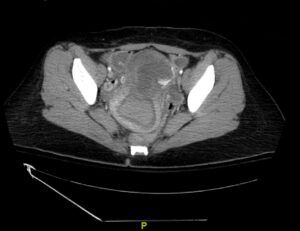

Iatrogenic Uterine Perforation. CT Unannotated. JETem 2024